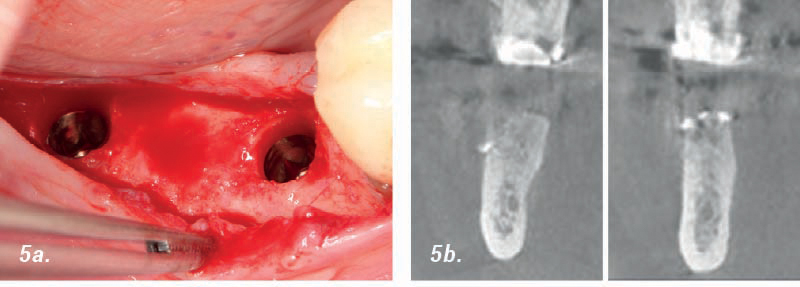

• 5a. Se utilizaron implantes con un ancho de 4 mm. colocados en lugares protésicamente designados.

• 5b. Después de 6 meses: Tomografía volumétrica digital (TVP) muestra suficiente cantidad de hueso recién formado.